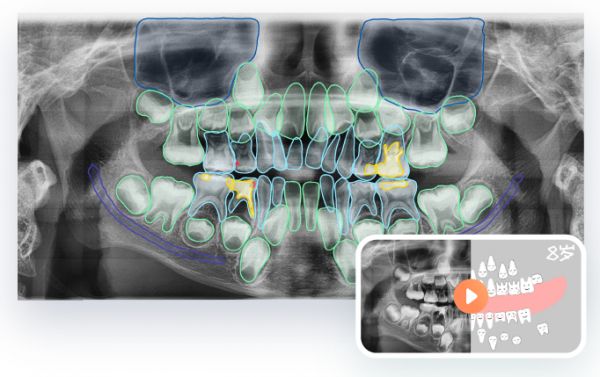

DeepCare开发的口腔智能系统

目前产品的应用模块分别为:口腔全景片、三维影像的AI智能分析,进展模拟,健康报告智能出具,治疗方案设计等,涵盖口腔诊疗全流程。尤其是影像分析模块,能够智能分析处理全景片、根尖片、头影测量片、锥形束CT等不同类型口腔影像。同时,产品对市场需求量大的几个领域(预防、正畸、种植、修复及儿童口腔等),会进行持续研发,已推出儿童口腔评估模块。

DeepCare 儿童口腔评估系统